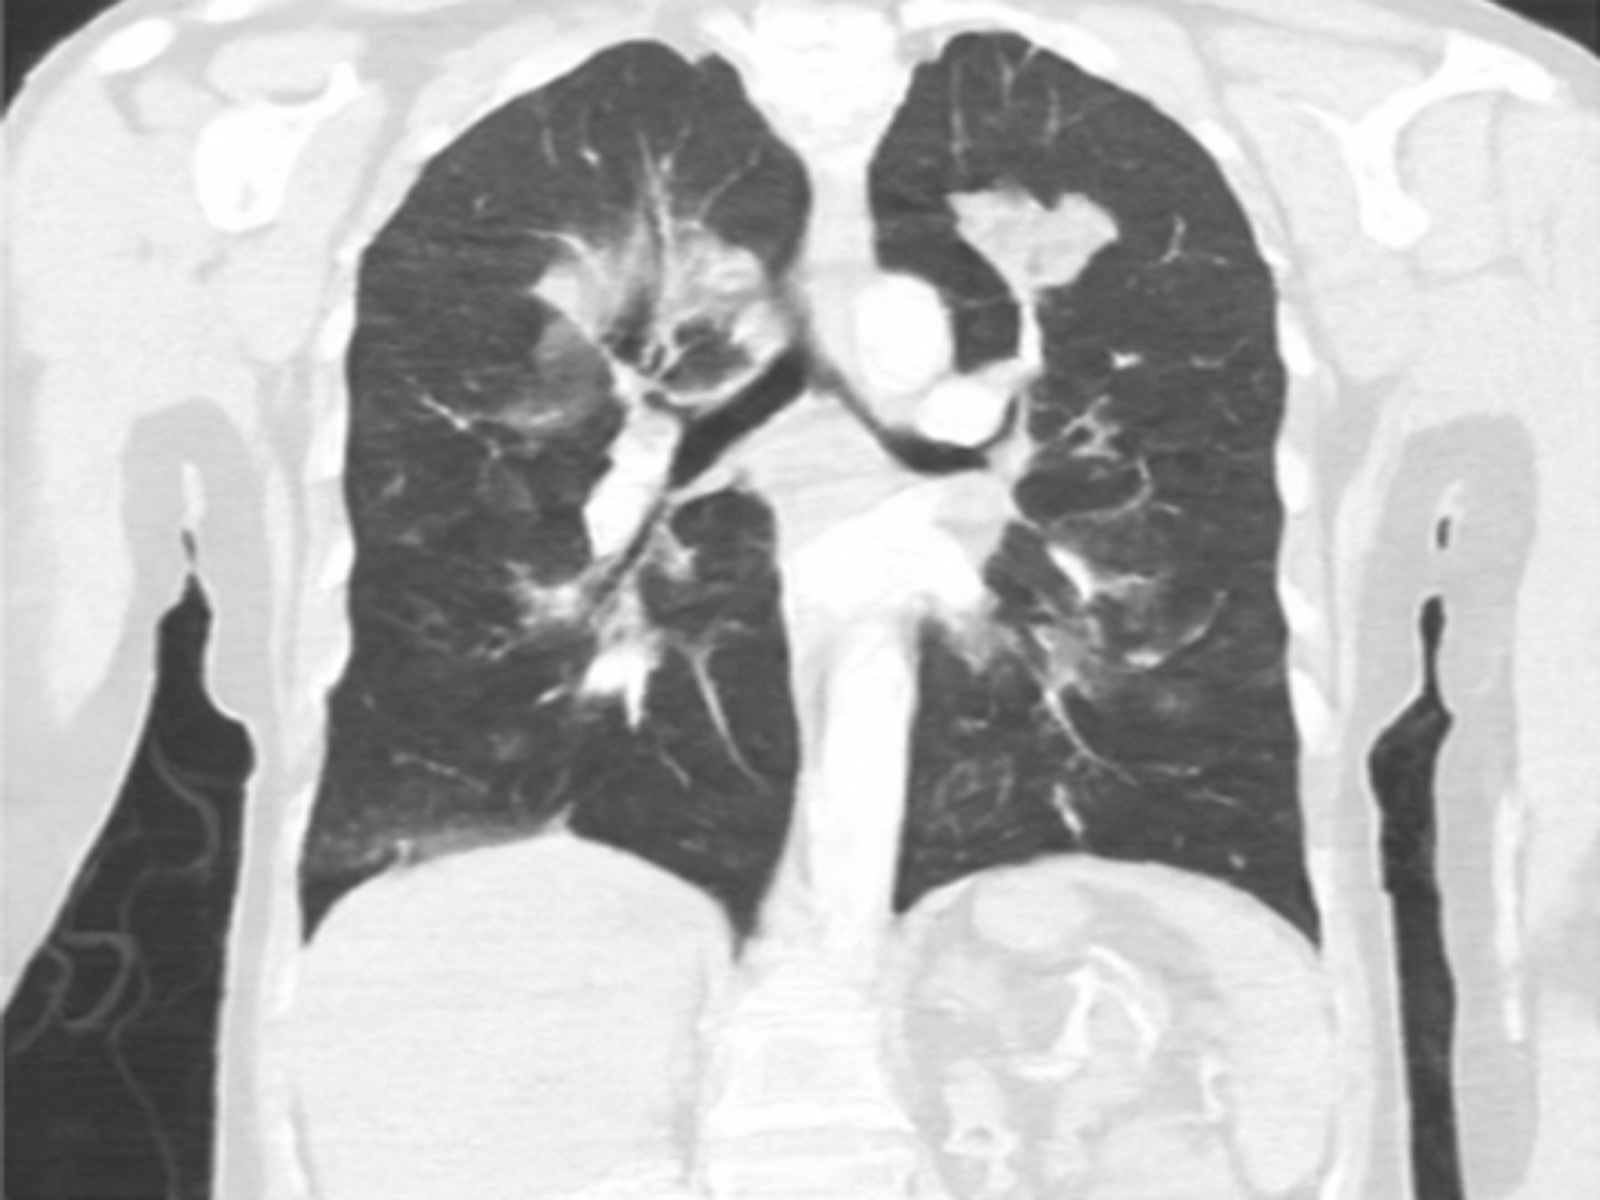

Infectious Masquerade: Mucinous Adenocarcinoma of the Lung Presenting as Pneumonia

Ashok Arbat, Diti Gandhasiri, Sweta Chourasia, Swapnil Bakamwar, Parimal Deshpande doi: 10.5505/respircase.2026.83446 Pages 43 - 46 |